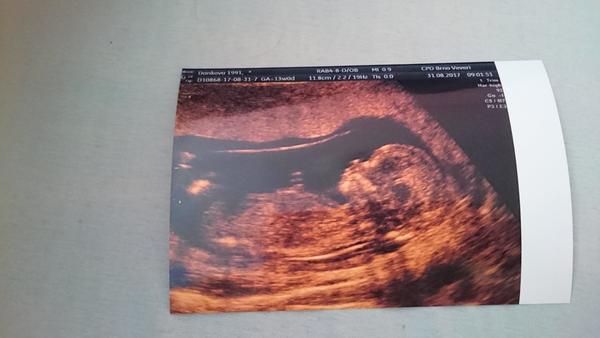

@kris5 tady přikládám fotku mého prvního děťátka z prvního screeningu chlapečka a je to Matyášek ❤

@spokojena_maminka děkuji třetí princ no😁já těm pohlavním hrbolkum nevěřím,všichni tvrdili že holka u mne i já to viděla a je to kluk 😂chlap prej že čtvrté bude holka ,ale má smůlu už stačilo a plodovka taky 😝